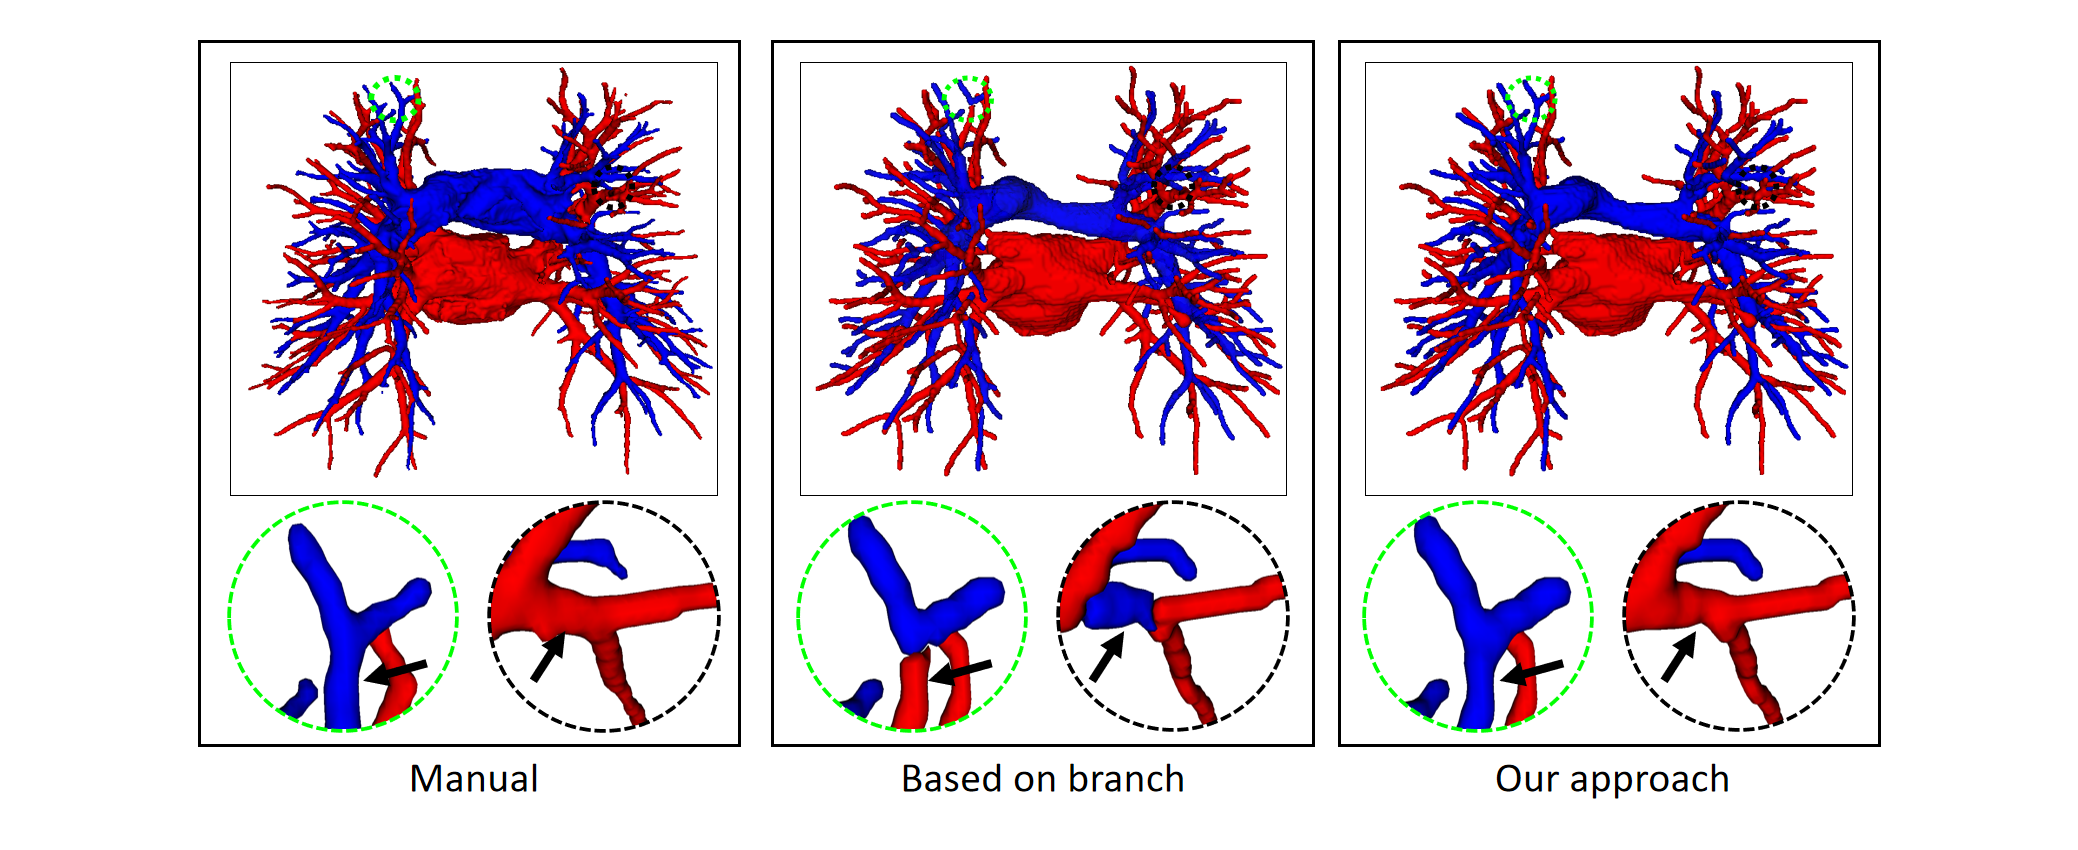

4.2.2 Topological postprocessing optimizer

To prove that the proposed topology optimizer is reasonable, we design different topology strategy optimizer to compare and analyze the experimental results. This approach includes the following: the precision of Twin-Pipe network (based on particle), the precision of topology branch refining (based on branch), the precision of topology subtree refining (based on subtree), and the refinement precision of the proposed topology optimizer. Table 3 shows an overview of the accuracy in all cases of the different topology strategy optimizers and reports on the sensitivity and specificity. The table 3 shows that our method is superior to branch-based and subtree-based topology optimizers, whose accuracies are 96.2%, 95.3%, and 93.2%, respectively.

Finally, the topology optimizer extracts the topology subtree and topology branch refinement results by the method in Section 2.3. The results of a topology subtree and topology branch are shown in Fig. 9. Then, we use topology subtrees and topology branches for postprocessing. As shown in Table 3, the proposed topology optimizer is superior to the subtree-based and branch-based topology optimization in accuracy. Fig. 14 and 15 show the reconstructed results of different topology strategy optimizers. The results in Fig. 14 show that when the number of points on the branch is small, and the branch-based topology optimization method is prone to predict errors. This finding is mainly because the branch-based refinement strategy focuses on the relationships within the branches and ignores the topological relationships between branches. As shown in Fig. 15, topology optimization based on subtree strategy is prone to prediction errors in the case of arterial-vein intersection. This finding is mainly because the arterial/venous intersection point in the extraction process of topological subtree is easily mistaken for the bifurcation point of arterial subtrees due to the complex structure of the vascular tree, arteries and veins interweave, and finally the venous branches are classified as arterial subtrees, resulting in the classification error.